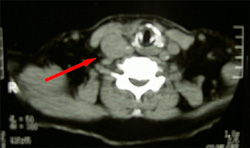

甲状腺乳頭がん |